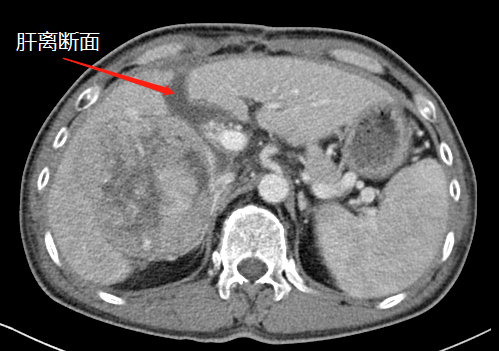

第一次術后,結(jié)扎門靜脈劈開肝臟

左肝增生,第二次手術切除腫瘤

“9月底,在第一階段手術中,我們先將患者的右側(cè)門靜脈結(jié)扎(肝的血液供應通過門靜脈和肝動脈進行),保留肝動脈、肝靜脈和膽管的完整性,然后沿肝中裂將肝臟的左右葉徹底劈開?!睋?jù)胡偉介紹,人體肝臟具有很強的再生功能,結(jié)扎門靜脈右支后左側(cè)肝臟由于過量的血液供應短期內(nèi)迅速增大;同時將患者的左右肝臟離斷,降低了腫瘤侵犯左側(cè)肝臟的可能。

第一次手術后

經(jīng)過20天左右的“養(yǎng)肝”,經(jīng)CT復查顯示,患者的左側(cè)肝臟體積已增長至42.8%,這時候,也就達到了我們說的“養(yǎng)大好肝、再切病肝”,因為此時好肝已經(jīng)足以維持患者身體的運轉(zhuǎn)需要。